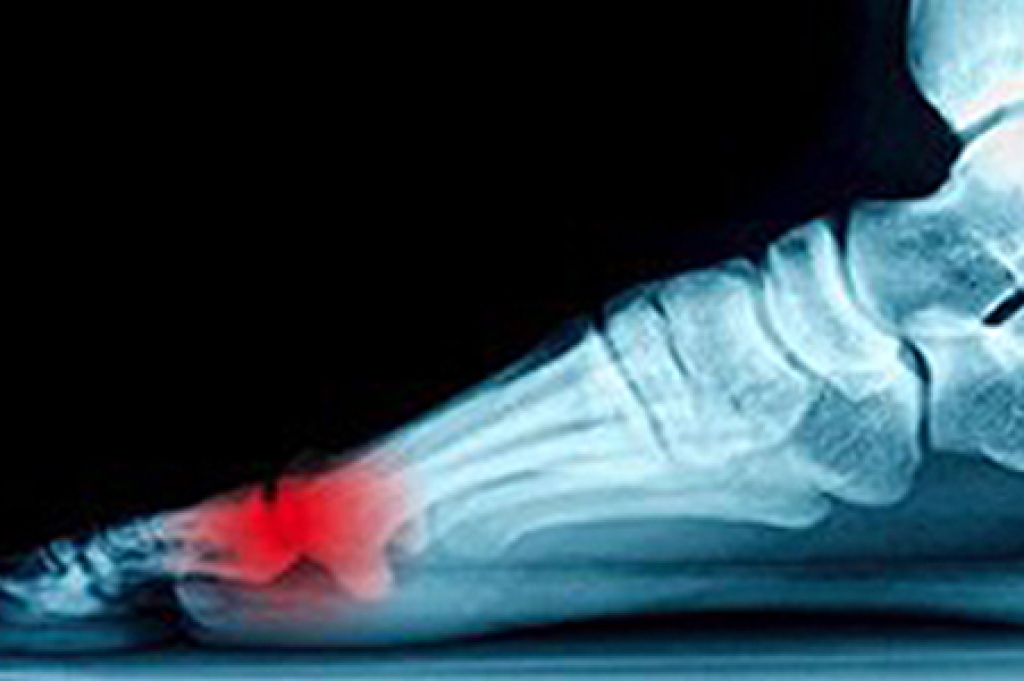

To figure out the cause of foot pain, podiatrists utilize several different methods. This can range from simple visual inspections and sensation tests to X-rays and MRI scans. Prior medical history, family medical history, and any recent physical traumatic events will all be taken into consideration for a proper diagnosis.